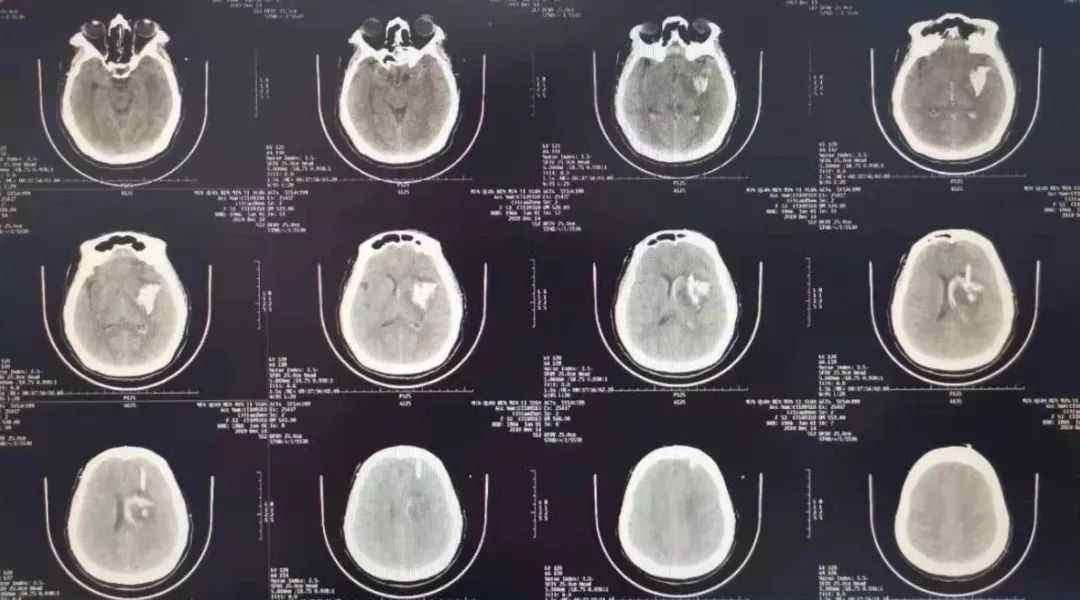

ct提示左侧基底节,丘脑,颞叶,枕叶广泛性脑出血.